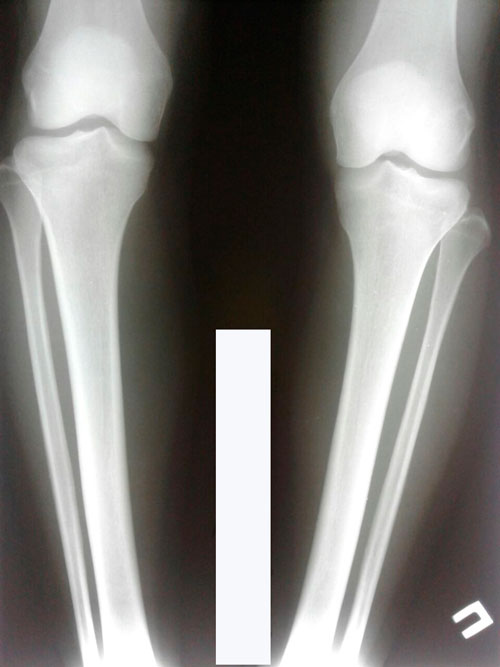

10ый день после операции- сняли швы и поменяли перевязки. Девочки, кто не знает, шов накладывают ниже колена, где делают небольшой горизонтальный разрез (около 1,5 см) для того, чтобы сделать полную остеотомию. Простым языком- чтобы сломать кость/или разрубить, не знаю, как правильнее сказать

Но знаю, что используют дрель для того, чтобы установить спицы

12.04.2018. 15ый день после операции. Так как у меня левая нога кривее правой, мне правую ногу крутили 3 дня, а левую - шесть дней. Но левая все равно чуть-чуть не догоняла правую, КН помимо положенных четырёх круток на левой ноге подкрутил еще левую ногу снова, причём нормально так)) я аж почувствовала мощную боль. Боль была в голени в месте перелома, в колене, в бедре(мощно болело бедро), в тазобедренном суставе, в копчике и даже болел лобок. Я прям чувствовала эту одну боль в этих местах. Ночью я вообще не сомкнула глаз, ночь была такой длинной и такой тяжёлой, и даже обезболивающий укол перед сном мне не помог(Кеторол), до 6 утра я промучилась и в 6:30 снова поставили укол. Боль немножко утихла и я поспала час. Потом пришёл на обход КН и сказал отдохнуть от круток.